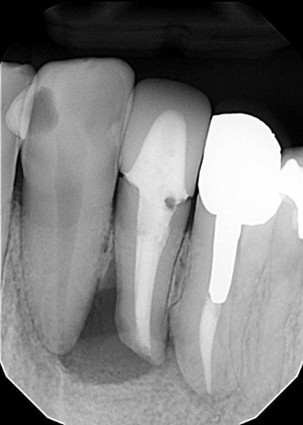

| 主訴 | 膿で腫れて痛みが強い、他の歯医者で抜歯しかないと言われ相談で来院 |

| 状態 | 自発痛もかなり強く、写真のように膿が溜まって腫れ上がっている状態 |

| 治療内容 | X写真から根先部の根先病変が原因と思われるため、根管治療を行った。 骨成長因子を用いて、骨の再生を促した。 結果、2年経過後病変の大きさが1/3まで縮小し、骨の再生が認められる。 本人も症状や違和感がなくなったため、一時的に補綴物をセラミックで行った。 |

| 料金 | 根管治療10万円、ファイバーコア2万円、EーMAX11.5万円 |